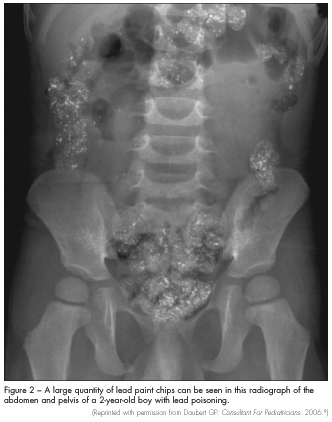

Imaging studies. Abdominal radiography may show the presence of radiopaque flakes, which is a clear indicator of pica (Figure 2). Radiographs of the long bones may show “lead lines.”2 Lead lines—which are abnormal calcium deposits, not actual lead deposition—may be detected at the distal metaphysis in children with lead levels greater than 45 µg/dL; these represent growth arrest associated with long-term lead exposure. This radiological finding is not required for diagnosis. Head CT scanning may be needed in patients who present with altered mental status to exclude cerebral edema and structural lesions.